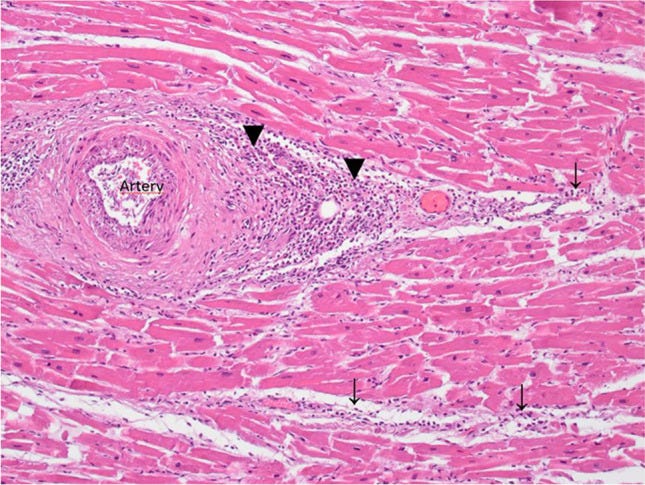

In 13 deceased, the cause of death was attributed to preexisting diseases while postmortem investigations did not indicate a causal relationship to the vaccination. In one case (case 6), myocarditis was found to be the cause of death (Fig. 1). A causal relationship to vaccination is possible, but cannot be proven beyond doubt. A competing cause of death was found to be severe pre-existing cardiac changes.

Fig. 1

Case 6 with myocarditis with lymphocytic and plasmocytic infiltration of the perivascular space (black down-pointing triangle) and the myocard (downward arrow) (H&E, Orig. Magn. 100 ×)

Regarding our investigated case of myocarditis, the period between the 2nd vaccination with a COVID-19 vaccine and the time of death was 11 h, which is also quite short. A causal relationship to vaccination was considered possible, but could not be proven beyond doubt.